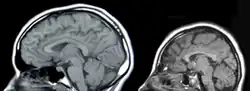

There are two parts of the nervous system: the central nervous system (CNS) and the peripheral nervous system (PNS). General body functions are supervised by the central nervous system (CNS), which includes the brain and spinal cord. The PNS delivers motor signals to control body activities and receives sensory data from the CNS. The PNS It is made up of nerve fibers arranged into nerves. The PNS's autonomic nervous system (ANS), whose sympathetic and parasympathetic branches preserve homeostasis and regulate involuntary physiological functions.[1]

Tissue Engineering The need for neural tissue engineering arises from the difficulty of the nerve cells and neural tissues to regenerate on their own after neural damage has occurred. The PNS has some, but limited, regeneration of neural cells. Adult stem cell neurogenesis in the CNS has been found to occur in the hippocampus, the subventricular zone (SVZ), and spinal cord.[15] CNS injuries can be caused by stroke, neurodegenerative disorders, trauma, or encephalopathy. A few methods currently being investigated to treat CNS injuries are: implanting stem cells directly into the injury site, delivering morphogens to the injury site, or growing neural tissue in vitro with neural stem or progenitor cells in a 3D scaffold.[16] Proposed use of electrospun polymeric fibrous scaffolds for neural repair substrates dates back to at least 1986 in a NIH SBIR application from Simon.[17] For the PNS, a severed nerve can be reconnected and reinnervated using grafts or guidance of the existing nerve through a channel.[18]

There are four main causes of CNS injury: stroke, traumatic brain injury (TBI), brain tumors, or developmental complications. Strokes are classified as either hemorrhagic (when a vessel is damaged to the point of bleeding into the brain) or ischemic (when a clot blocks the blood flow through the vessel in the brain). When a hemorrhage occurs, blood seeps into the surrounding tissue, resulting in tissue death, while ischemic hemorrhages result in a lack of blood flow to certain tissues. Traumatic brain injury is caused by external forces impacting the cranium or the spinal cord. Problems with CNS development results in abnormal tissue growth during development, thus decreasing the function of the CNS.[16]